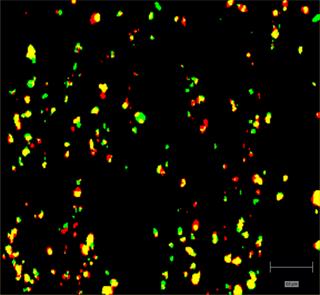

Rapidly generate images of your formulations with StreamLine™. This uses line focus illumination, allowing you to use higher laser powers without risk of sample damage, thereby reducing experiment times.

Generate images of formulations

Ensure your chemical images are representative; use Renishaw's StreamLine. You can change resolution to suit your domain size and, because Renishaw's WiRE software can cope with massive data files, you can analyse over the entire sample surface. Powerful Renishaw features, such as Slalom (to ensure the whole surface is sampled) and HD imaging (to get crisp clear images), provide all the options you need, whatever your formulation.